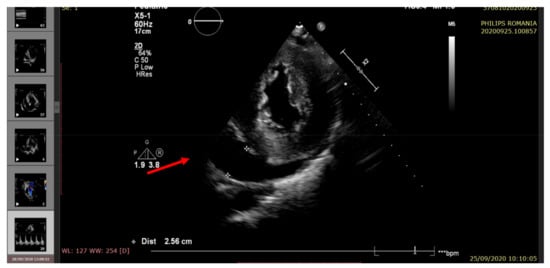

| Right ventricular ejection fraction RV EF (%) | >60 | 55 | 50 | 55 | 45 |

| Left ventricular ejection fraction LV EF (%) | >60 | 60 | 35 | 45 | 25 |

| Pericardial fluid (edge) | <5 mm | Small (6 mm) | Raised (20 mm) | Moderate (14 mm) | Large (22 mm) |

| Pulmonary hypertension (echocardiographic criteria) | Normal | Mild | Moderate | Mild | Moderate/severe |